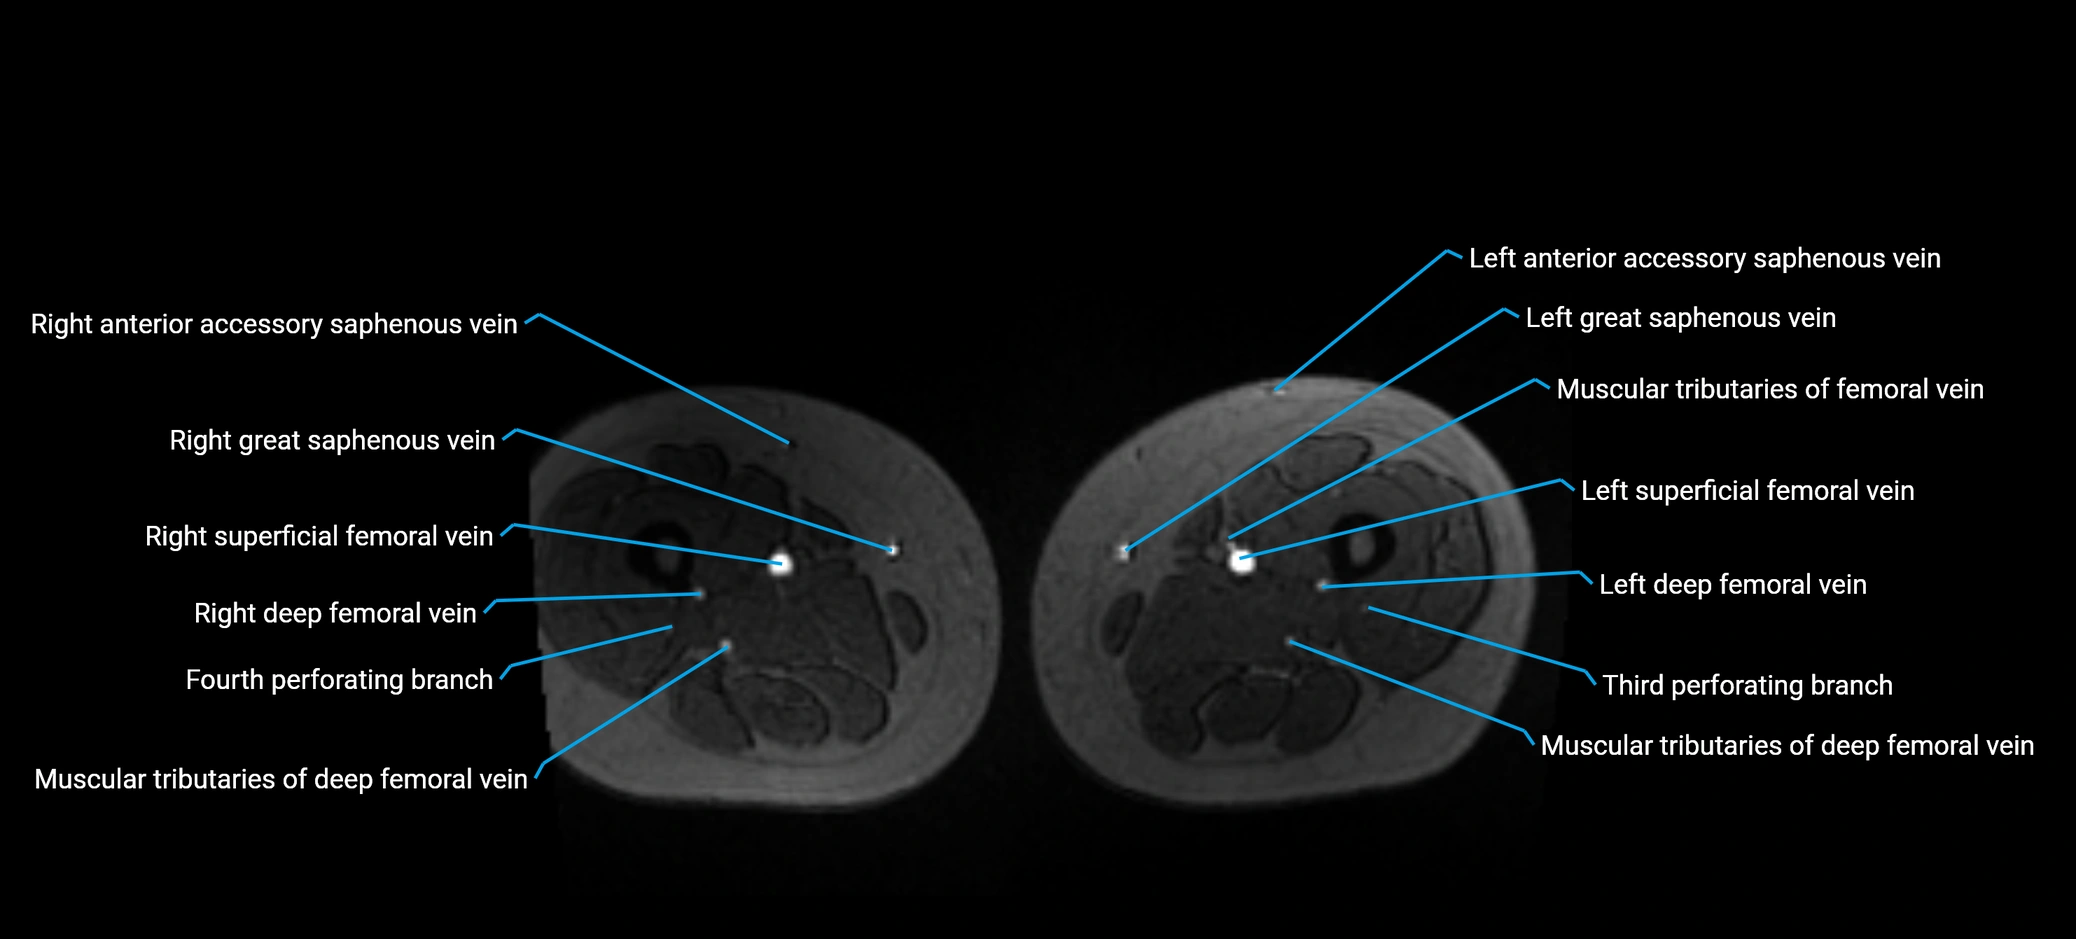

MRI image

image